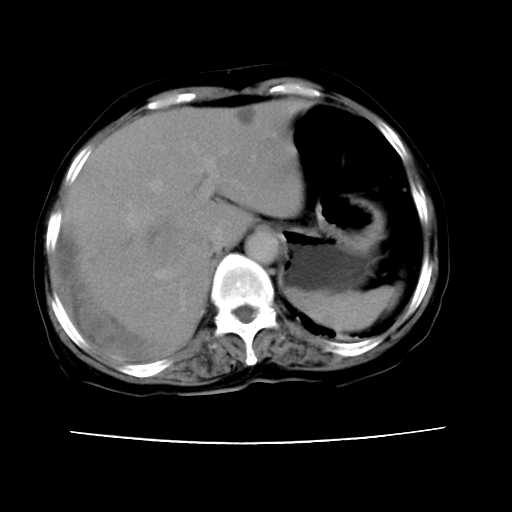

2008-11-10ct平扫(其间去中山医院诊治未行特殊治疗)

2008-11-10ct平扫见并肝内、血膜下血肿基本吸收,肝内低密度灶缩小。此时再做增强ct应有显着意义。对患者/医者都好!

从平扫+增强及治疗后复查片,病变明显缩小,不考虑肝癌出血可能,还是考虑为良性病变可能性大;单纯血肿并包膜下积液吧,病变强化没法解释,肝血管破裂出血吧,增强不符合典型血管瘤的表现,良性肿瘤破裂出血吧,复查片看来好像也不太支持(没做强化也不太好说)。本人还是考虑单纯肝内血肿并包膜下积液,强化是不是血管有外渗。

患者自6月至11月,如果是肝癌,没有经过特殊治疗,想必应该会有所进展吧,而不是ct所见,反而似有病灶减小的趋势。建议增强。

同意肝内肿块破裂致腹部疼痛,但不考虑肿瘤及血管瘤,增强不是血管瘤的特点,肿瘤半年时间内未经特殊治疗竟然快消失?考虑炎性改变或脓肿或寄生虫